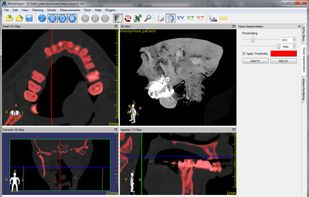

Weasis is a multipurpose standalone and web-based DICOM viewer with a highly modular architecture. It is a very popular clinical viewer used in healthcare by hospitals, health networks, multicenter research trials, and patients.

Weasis is a multipurpose standalone and web-based DICOM viewer with a highly modular architecture. It is a very popular clinical viewer used in healthcare by hospitals, health networks, multicenter research trials, and patients.